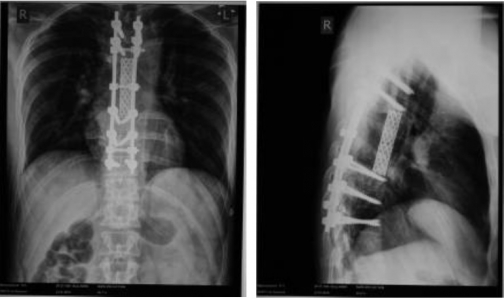

Однако протезирование метастазированных шейных позвонков в таком масштабе до сих пор никто не выполнял. Сначала пациенту удалили дужки четырёх шейных позвонков (со второго по пятый) и титановыми винтами зафиксировали затылочную кость, первый шейный позвонок, седьмой шейный позвонок и первый грудной позвонок. На втором этапе были удалены тела пяти шейных позвонков с опухолью (со второго по шестой) и имплантат, который был там со времени более ранней операции в другом медицинском учреждении. Позвонки заменили специальной титановой трубкой, заполненной костным цементом. Спинной мозг и кровеносные сосуды оставили позади трубки.

Операцию по протезированию шейных позвонков проводили в два этапа. Сначала за 6 часов хирурги удалили пациенту дужки шейных позвонков — со второго по пятый, зафиксировали затылочную кость, а также 3 других позвонка - первый и седьмой шейные, а также первый грудной с помощью специальных титановых винтов и штанг. Во время второго этапа операции, длившегося 8 часов, мужчине удалили тела пяти шейных позвонков, пораженных опухолью (со второго по шестой), а также удалили установленный ранее в другой клинике имплантат. Затем хирурги заменили удаленные позвонки специальной сетчатой титановой трубкой, заполненной костным цементом — протезом тел позвонков.